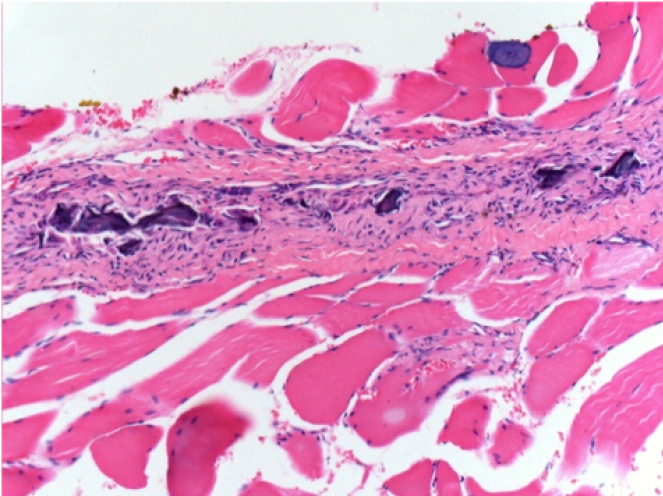

10

Iniezione Endopeel nel tessuto subcutaneo SC

Scatola 6

0.5 ml ( 5x 0.1ml): Iniezione SC di Endopeel nel tessuto pretibiale subcutaneo SC destro (Dx).

Sx:200x-Controllo-SC

Dx-Giorno10-SC-200X

Dx-Giorno30-SC-200X

Dx-Giorno90-SC-200X

Dx-Giorno210-SC-200X

Dx-Giorno210-SC-400X

Endopeel induce una miofibrolisi selettiva reversibile e una risposta infiammatoria approssimativamente nel periodo di 1 mese.

I cambiamenti dei tessuti muscolari sono quasi completamente reversibili.

Il muscolo é il posto migliore per iniettare Endopeel ,per la sua maggiore efficacità, il controllo e la durata della sua azione.

Nessuna necrosi ne ascesso sono stati osservati durante la sperimentazione.